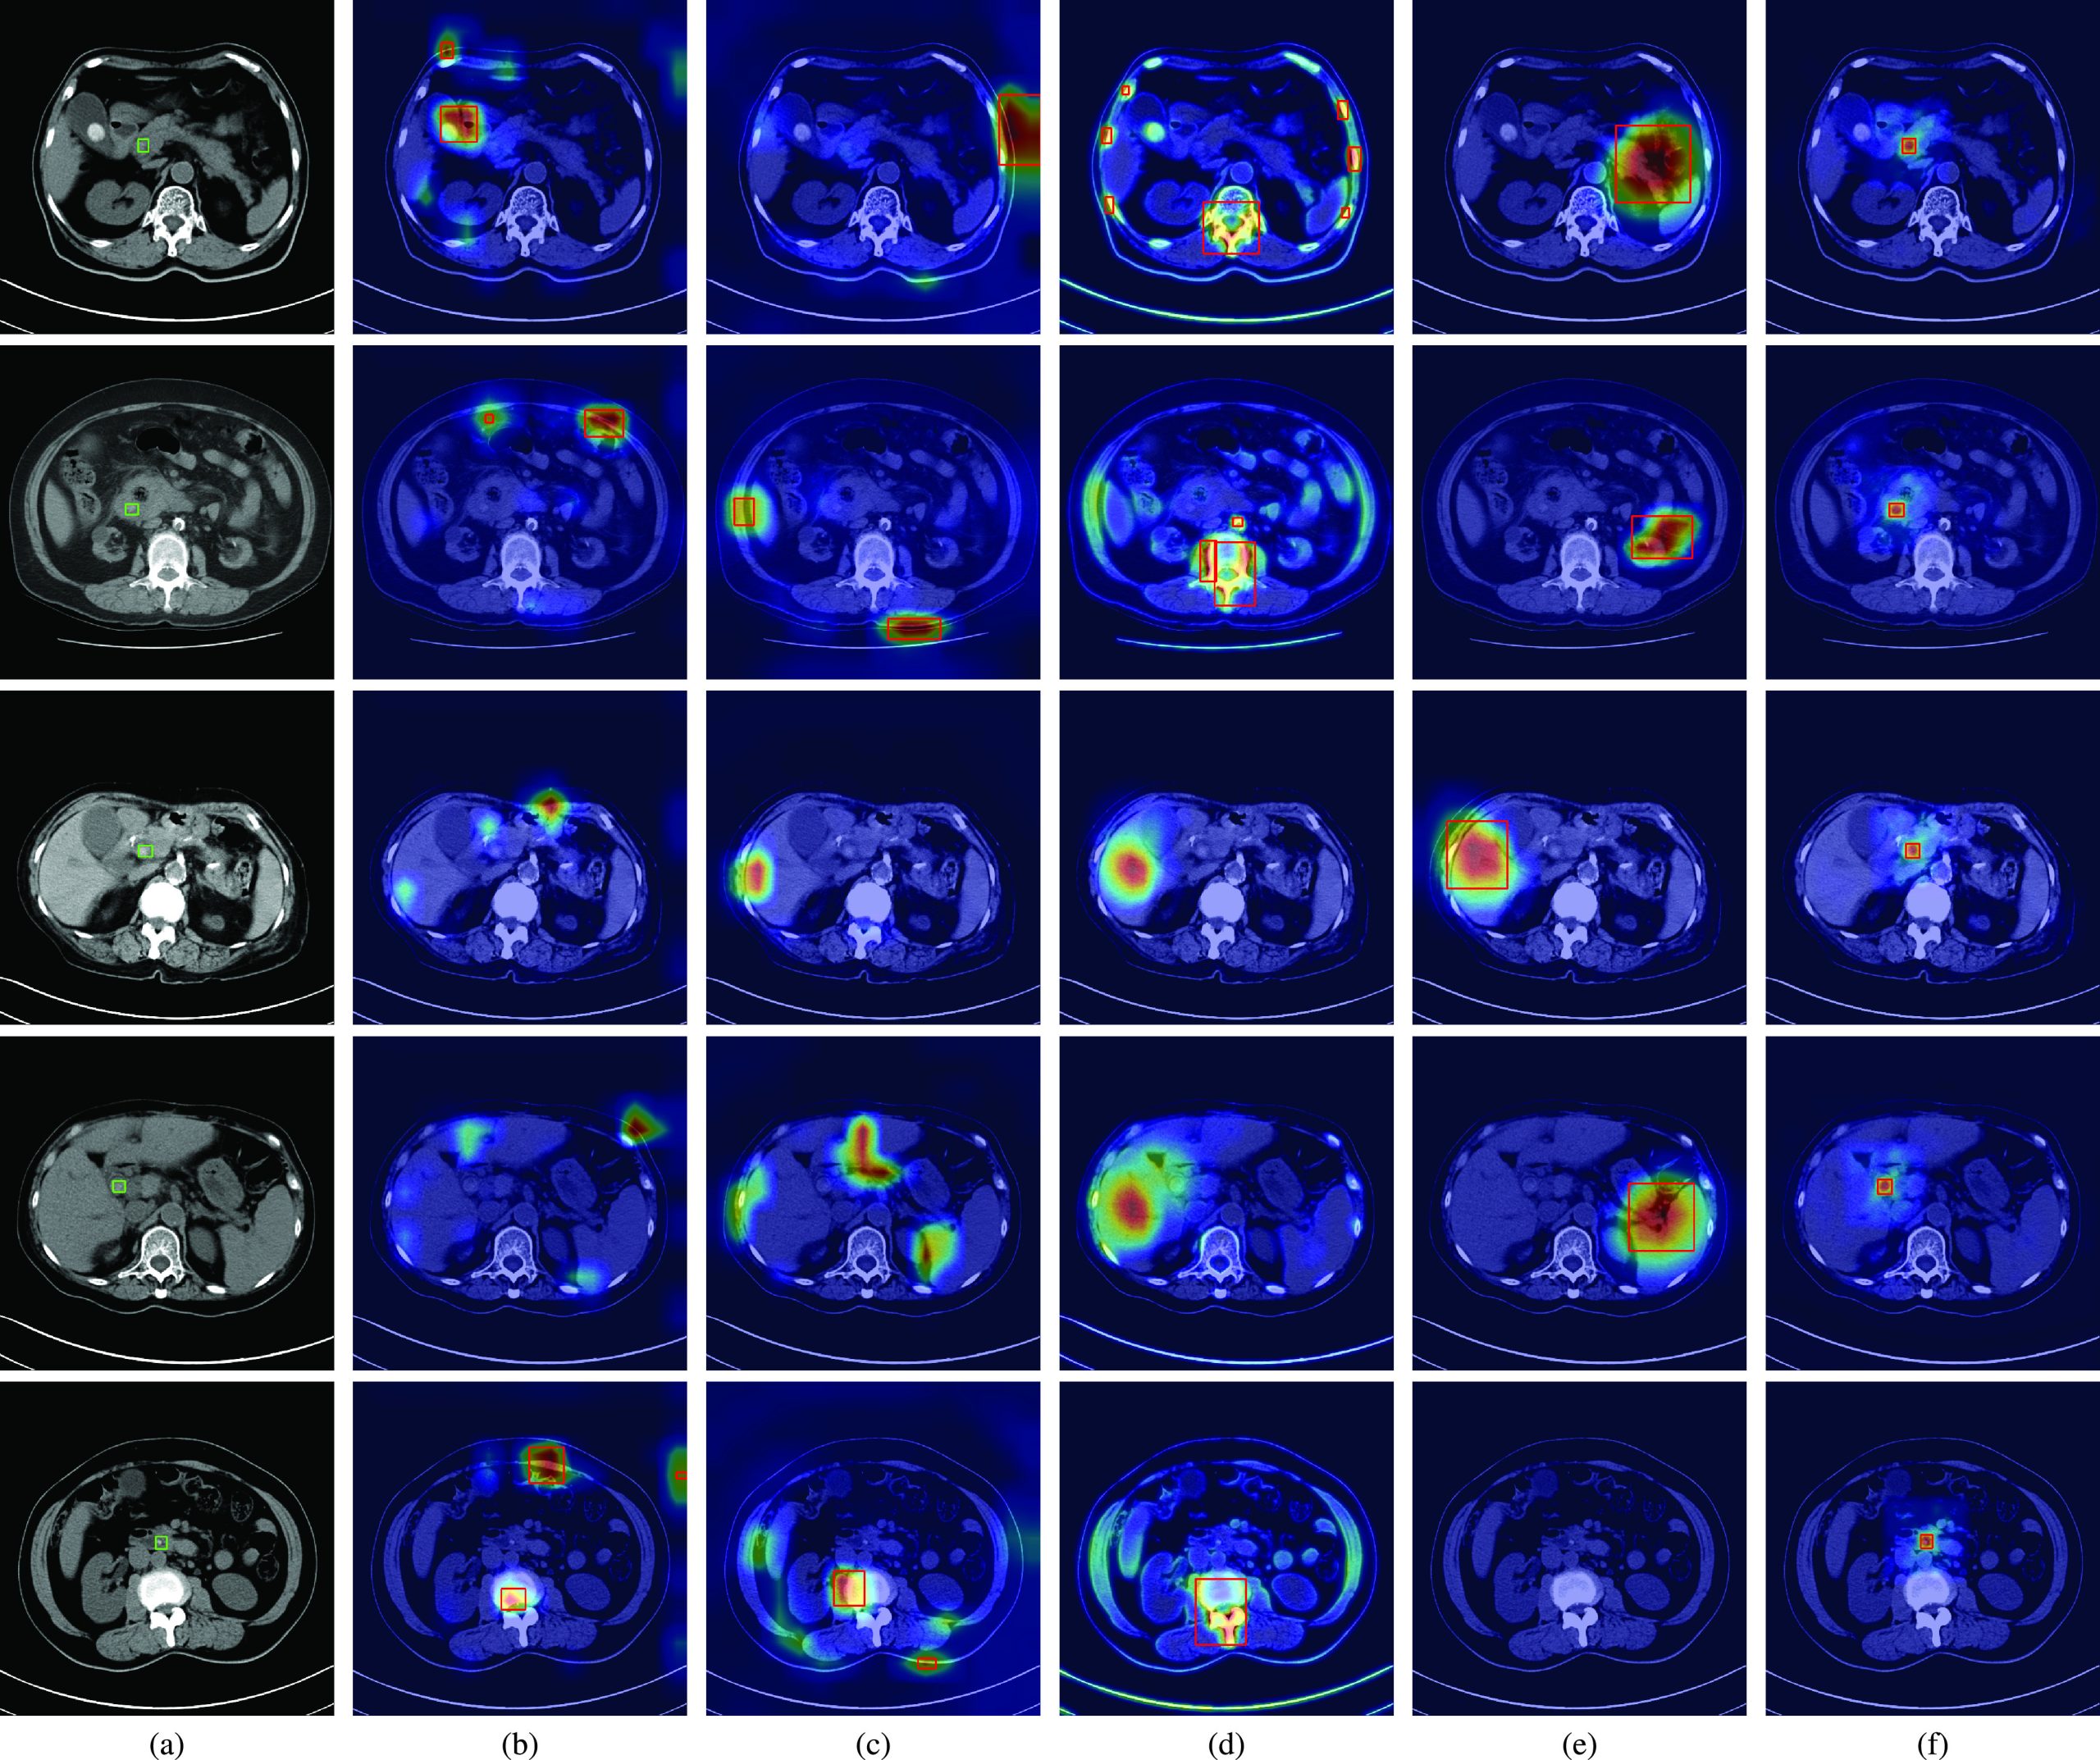

Fig. 3(a) shows the ground truth regions of CBD stones in CT scans by using green rectangles. The results of CAM, Grad-CAM, MS-CAM, SPA and the proposed method are shown in Figs. 3(b), (c), (d), (e), and (f), respectively. The same as the observations in Fig. 2(b), the salient feature responses of CAM are affected by bone regions for the second and fifth patients, and the gallstones of the first patient. Although CAM successfully classifies the CT scans of the first, second, and fifth patients as CT scans with CBD stones, the locations of detected CBD stones are incorrect compared with the ground truth. Because the CBD stones of the third and fourth patients are not clearly captured by CT scans, the learned salient features of CAM cannot represent the CBD stones for classification. Thus, miss-detection of CBD stones occurs for these two patients. Similar results can also be observed for Grad-CAM and MS-CAM in Fig. 3(c) and (d).

Compared with CAM based methods, SPA considers the restricted activation module to learn local object structure and self-correlation to refine localization maps. Thus, the salient features of SPA can focus on non-bone regions. Nevertheless, SPA still fails to correctly locate CBD stones compared with the ground truth for the first four patients as shown in Fig. 3(e). Because CBD stones are relatively small and are not clearly captured in CT scans, the modules of SPA are hard to learn local object structure of CBD stones from only image-level labels. As a result, the learned features of SPA cannot represent CBD stones for the fifth patient.

As shown in Table 3, the competing methods have low mIoU and AP values. Such results can be visually explained by the salient feature responses of these methods shown in Fig. 3(b), (c), (d) and (e), respectively. These competing methods focus on regions without CBD stones compared with the ground truth regions. Thus, the mIoU values of these methods are naturally low because the detected regions do not overlap the ground truth regions. In contrast, the visualizations shown in Fig. 3(f) reveal that the proposed method provides an interpretable AI model which truly focuses on CBD stones. The cooperation of losses and the whole network provides a novel weakly-supervised learning way to learn salient features to represent CBD stones. Thus, the mIoU and AP values of the proposed method are significantly better than those of the competing methods.